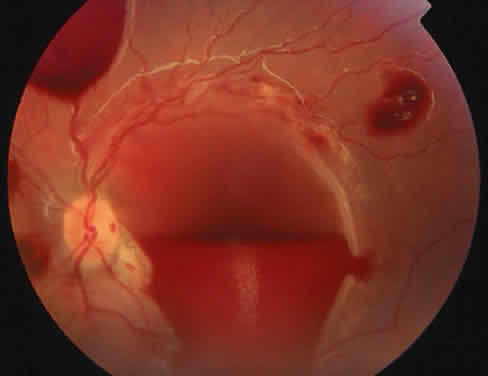

The most common ocular manifestations of TTP include papilledema, extraocular muscle palsies, and visual field defects, which usually are secondary to concomitant CNS involvement.75 Retinal findings consist of hemorrhages, retinal vascular occlusions, and serous detachments76,77 (Figs. 8 to 10). The cause of the serous detachments appears to be focal occlusion of the choriocapillaris resulting in retinal pigment epithelial damage and blood-retinal barrier disruption.76,77 Findings on fluorescein angiography are characterized by focal areas of nonperfusion of the choriocapillaris associated with late leakage into the subretinal space76 (Fig. 11). This is consistent with histopathologic studies that show occlusion of the choriocapillaris and large choroidal vessels, presumably by fibrin, with overlying necrosis of thepigment epithelium.75,76 TTP also has been linked in one case report with Purtscher retinopathy.78

Fig. 10. A 42-year-old woman with thrombotic thrombocytopenic purpura and neurosensory retinal detachments. (Courtesy of Jerry Neuwirth, MD.)

Fig. 11. Fluorescein angiogram of patient with thrombotic thrombocyto-penic purpura showing late choroidalhyperfluorescence caused by focal areas of choriocapillaris nonperfusion. (Courtesy of Jerry Neuwirth, MD.)

Clinically, the development of serous retinal detachments usually is associated with exacerbations of TTP and the development of acute hypertension. Although serous retinal detachments have been described as a preterminal event, resolution of the detachments with subsequent pigment epithelial changes may occur when the underlying hypertension and thrombocytopenia are controlled.77